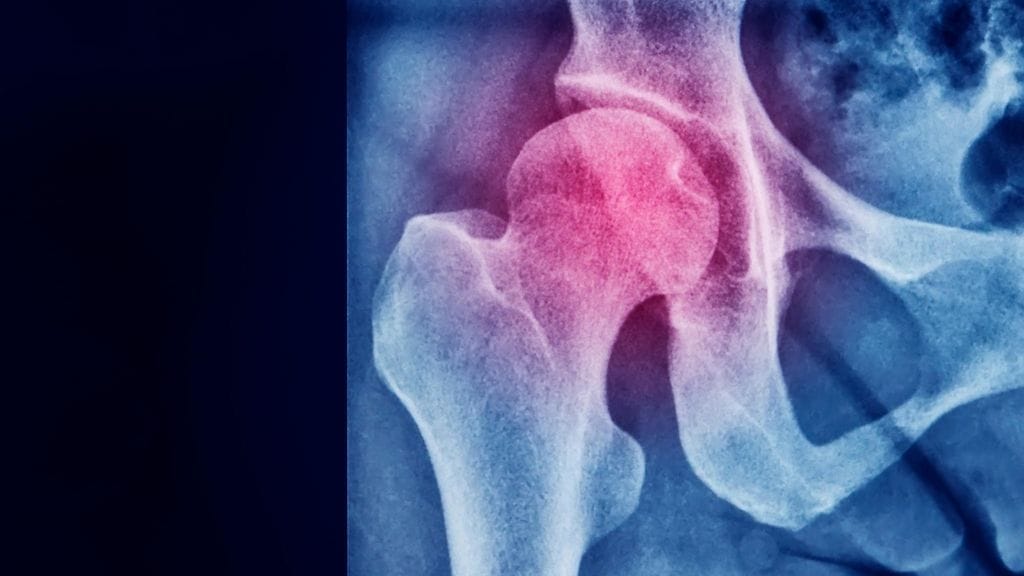

Yhdysvaltalaistutkijat mittasivat työtään varten 173 aikuisen, 35–50-vuotiaan henkilön luun mineraalimäärää ja lujuutta. Tutkijat huomasivat, että 28 prosentilla miehistä ja 26 prosentilla naisista oli osteopeniaa. Osteopeniassa luun lujuus on heikentynyt, mutta vähemmän kuin osteoporoosissa. Osteopeniaa pidetään osteoporoosin esiasteena.

Tulokset ovat yllättäviä, sillä osteoporoosi on naisilla selvästi yleisempi kuin miehillä.